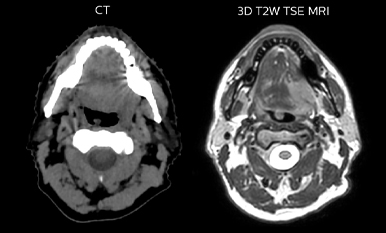

MR-based target contouring on 3D T2W TSE in transversal, sagittal and coronal planes.